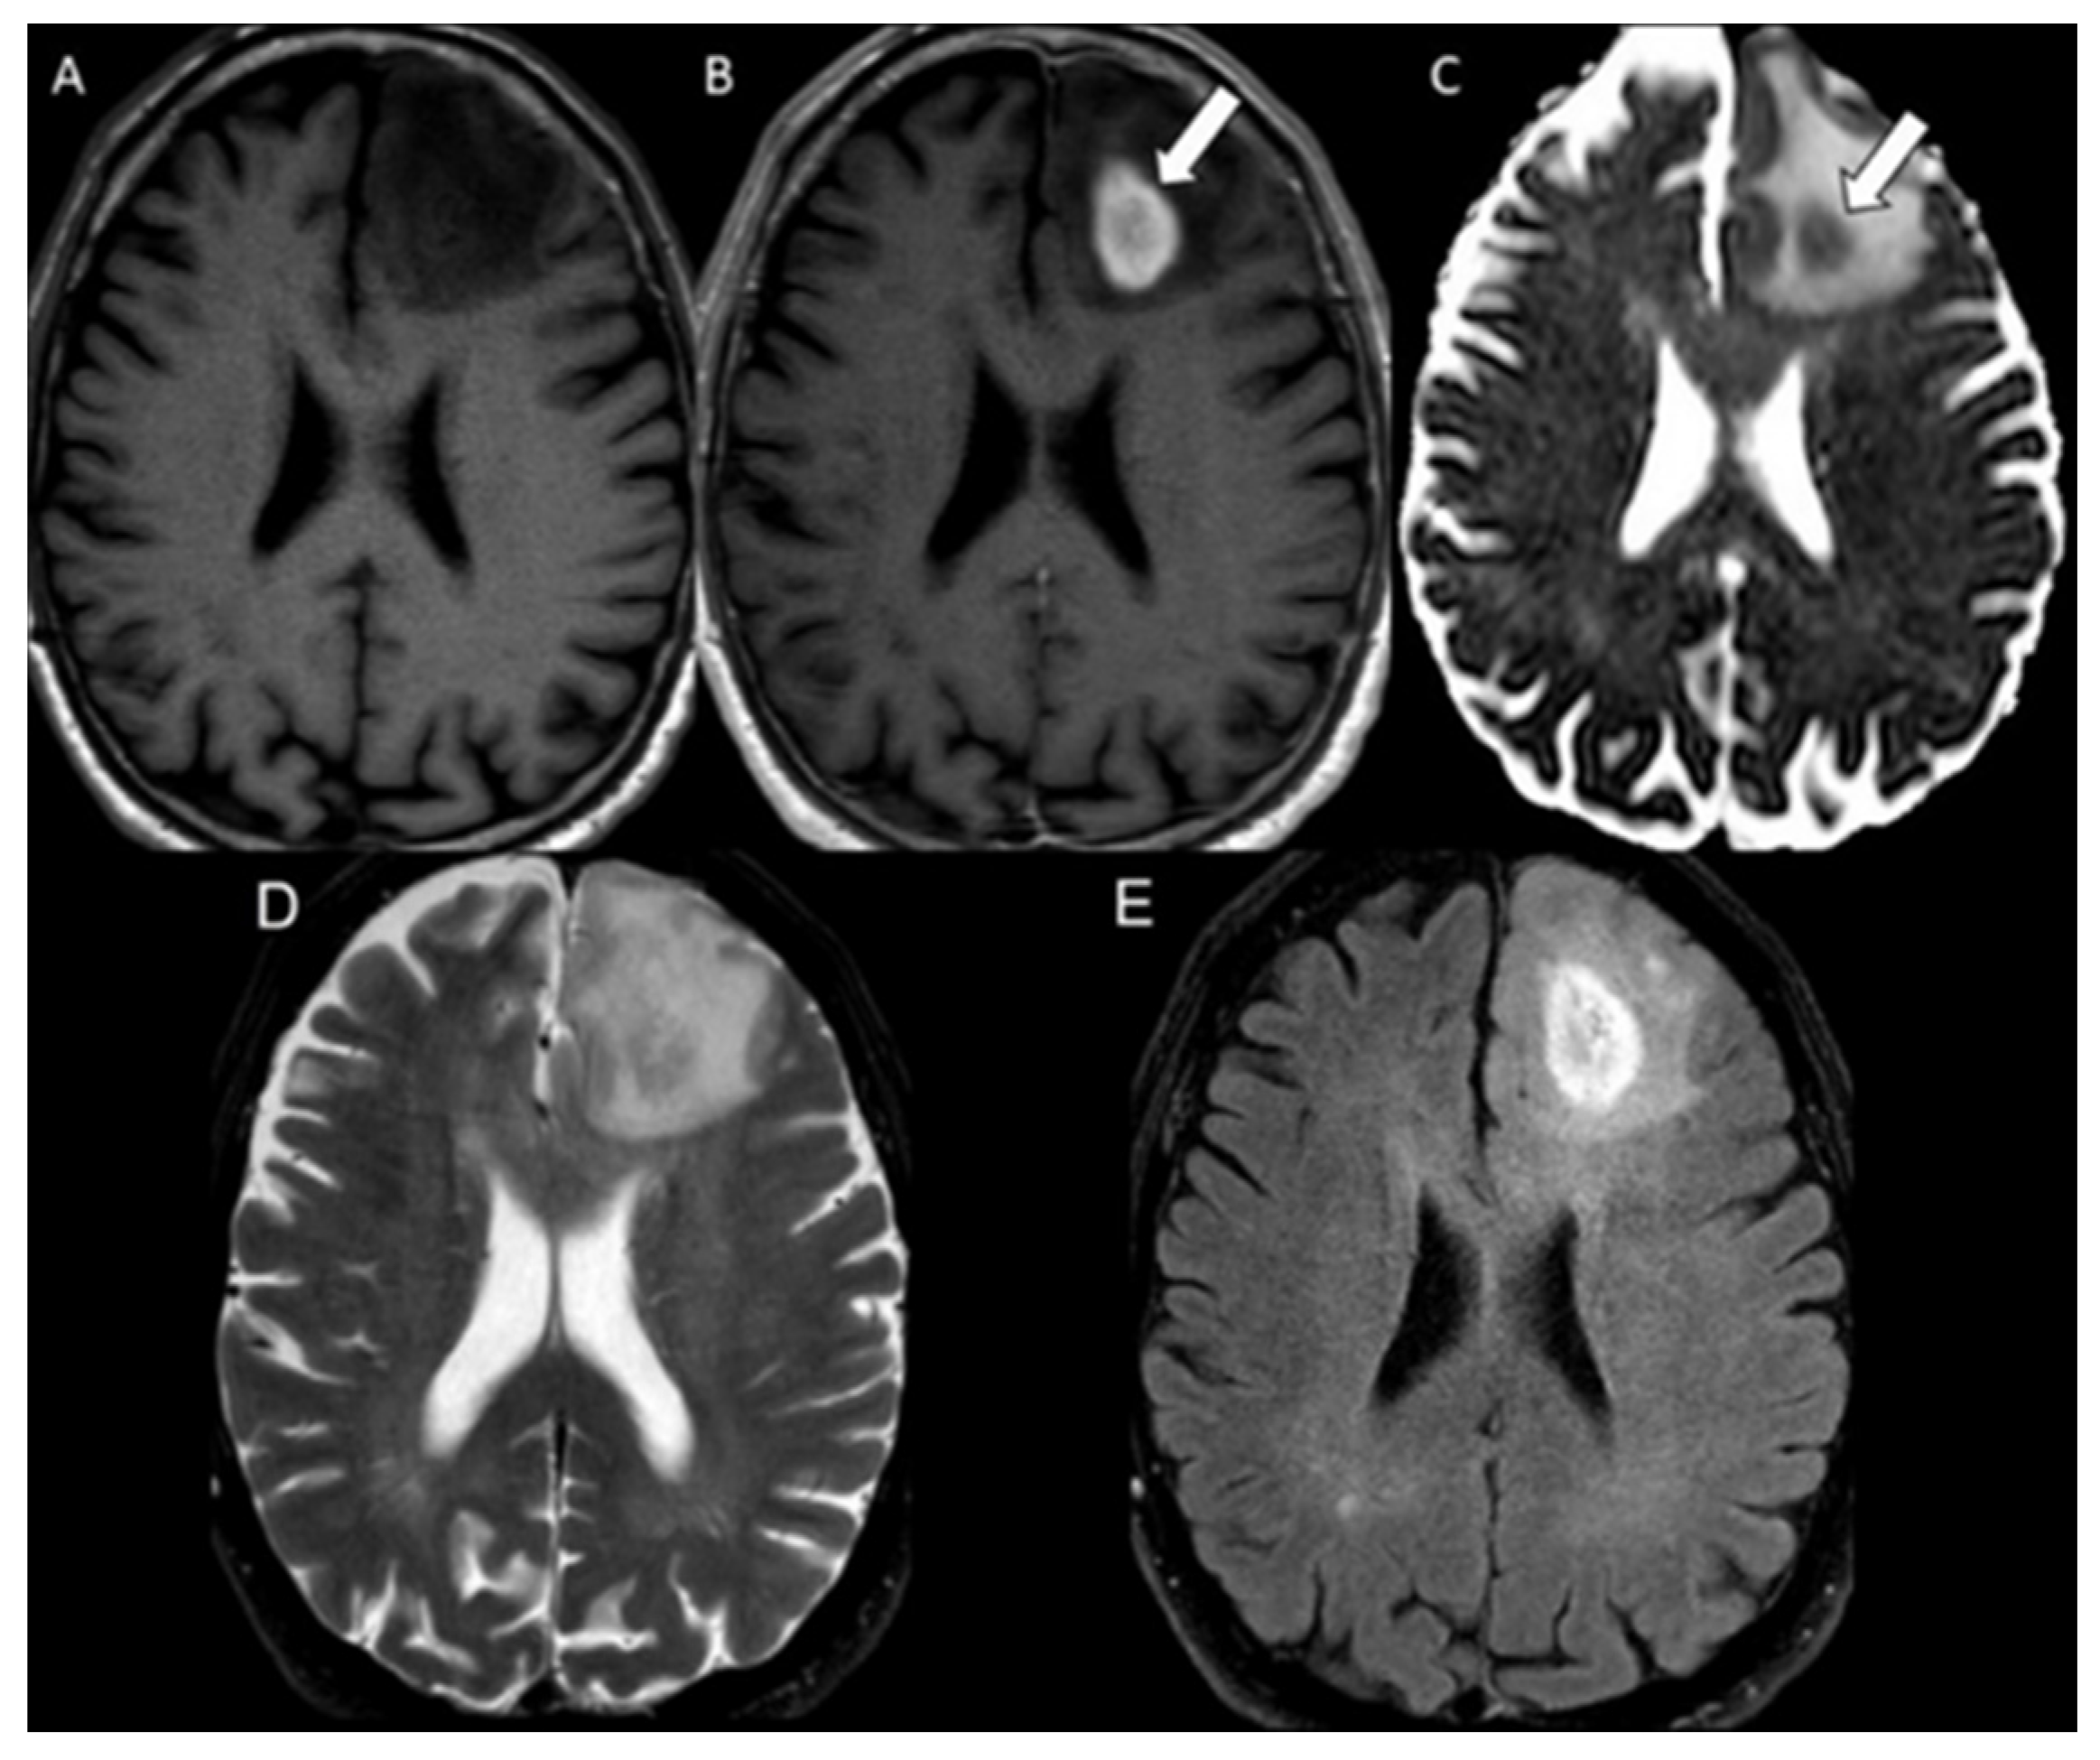

| Progressive glioblastoma | 49 | 1.07 ± 0.22 |

| Progressive glioblastoma | 49 | 752.8 ± 132.5 | 709.2 ± 63.5 | 0.08 |